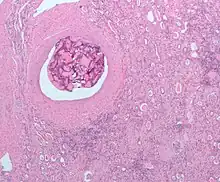

Il existe aussi des agents particulaires comme le Gelfoam, l'alcool polyvinylique ou les microsphères d'embolisation.

Enfin, on signalera la classe des dispositifs d'occlusion mécanique : coils et ballons détachables. Les coils sont généralement fait de platine et induisent la formation d'un thrombus à leur contact en raison de leur revêtement en polytéréphtalate d'éthylène.